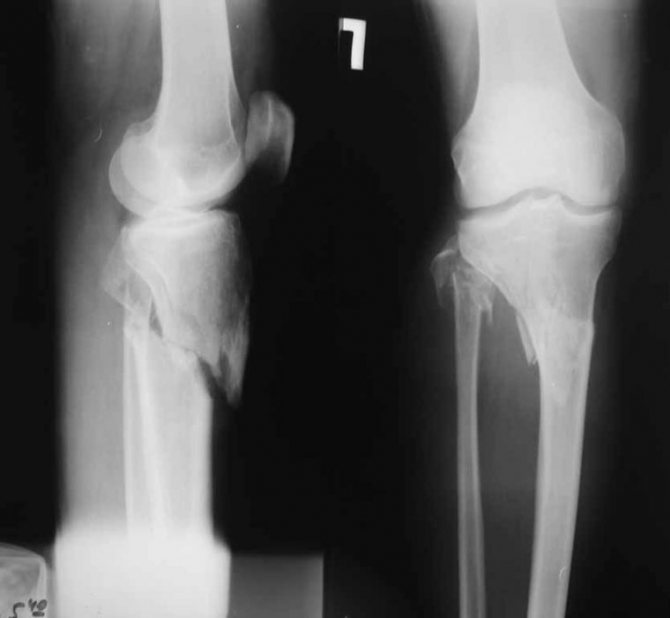

Очень важно своевременно диагностировать перелом кости голени, на основании полученных данных врачом рекомендуется дальнейшее лечение. Сразу после поступления пострадавшего в больницу его осматривает врач, диагностируя характерные симптомы, собирает обстоятельства получения травмы. В любой ситуации показано выполнить рентгеновский снимок обязательно в двух проекциях для более точной диагностики. При повреждении отдельных частей необходимо специфическое обследование, особенно если закрытый перелом голени без смещения.

Переломы малоберцовой и большеберцовой костей в области тела

При возникновении сомнений на рентгеновском снимке или переломе с большим количеством отломков показано проведение КТ. При помощи этого метода врач на срезах четко видит состояние костей голени, расположение и количество отломков.

Методы диагностики

Главный метод диагностики – рентген голени, а также области двух суставов (голеностопного и коленного). Данный метод позволяет увидеть состояние костей, определить вид перелома, визуализировать смещение отломков. На рентгене перелом выглядит как темная полоска между частями кости, которая может идти в любом направлении.

При закрытых переломах костей Г. (см. Переломы) наблюдаются патологическая подвижность, смещение и крепитация отломков, деформация Г., быстро нарастают отек, гематома, боль, нарушается функция конечности. Не столь яркие клинические проявления отмечаются при изолированных переломах костей Г. без смещения, когда может быть сохранена опороспособность конечности. При переломах диафиза большеберцовой кости центральный отломок обычно смещается внутрь и вперед, а периферический — назад и поворачивается кнаружи. Для уточнения диагноза большое значение имеет рентгенография костей Г. Рентгенограммы должны выполняться в двух проекциях на пленке крупного формата, т.к. уровни переломов большеберцовой и малоберцовой костей часто не совпадают. При прямом механизме травмы с локализацией перелома в верхней трети Г. (так называемые бамперные переломы) необходимо целенаправленно исследовать состояние связочного аппарата коленного сустава, клинические проявления повреждения которого иногда нивелируются. Переломы верхней трети Г. могут сопровождаться повреждением сосудов и нервов, кровотечением и посттравматическим отеком, который при сохранении целости фасций может быстро нарастать. В подобной ситуации требуется срочная фасциотомия.